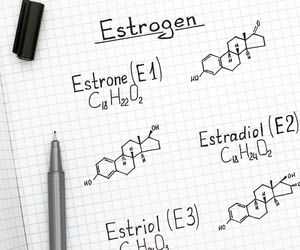

Hormony to związki chemiczne wydzielane przez struktury układu hormonalnego – gruczoły lub tkanki. Ich główną funkcją jest regulacja poszczególnych procesów fizjologicznych. Hormony mogą oddziaływać zarówno na tkanki położone w miejscu uwolnienia substancji (tzw. hormony lokalne), jak i aktywować procesy w tkankach oddalonych od miejsca sekrecji. Są wtedy transportowane przez krew lub limfę. Prawidłowe działanie układu hormonalnego jest niezbędne do funkcjonowania praktycznie wszystkich mechanizmów obecnych w ciele człowieka od trawienia, przez funkcje płciowe, aż po gospodarkę energetyczną.

W ciele człowieka funkcjonuje kilkanaście gruczołów dokrewnych wśród których można wymienić m.in. szyszynkę, tarczycę, wątrobę i trzustkę. Na cały układ hormonalny składa się kilkadziesiąt różnych hormonów, które pozostają ze sobą w stałej równowadze.